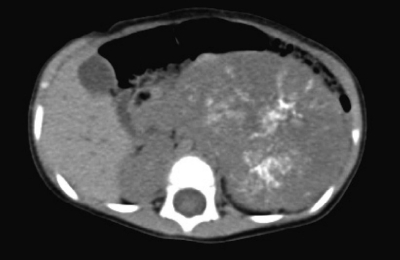

尿所見:蛋白(-)、糖(-)、潜血(-)、沈渣に白血球を認めない。血液所見:赤血球 428 万、Hb 11.1 g/dL、Ht 34 %、白血球 12,600、血小板 58 万。血液生化学所見:総蛋白 7.6 g/dL、総ビリルビン 0.2 mg/dL、AST 35 U/L、ALT9U/L、LD 589 U/L(基準 334〜742)、尿素窒素 7 mg/dL、クレアチニン 0.2 mg/dL、尿酸 2.7 mg/dL、Na 141 mEq/L、K3.9 mEq/L、Cl 104 mEq/L。免疫血清学所見:CRP 3.4 mg/dL、NSE 169 ng/mL(基準 10 以下)、α-フェトプロテイン(AFP)2.5 ng/mL(基準 10 以下)、尿中バニリルマンデル酸(VMA)96 μg/mgCr(基準 6〜11)。腹部単純CTと胸腹部造影CTとを示す。